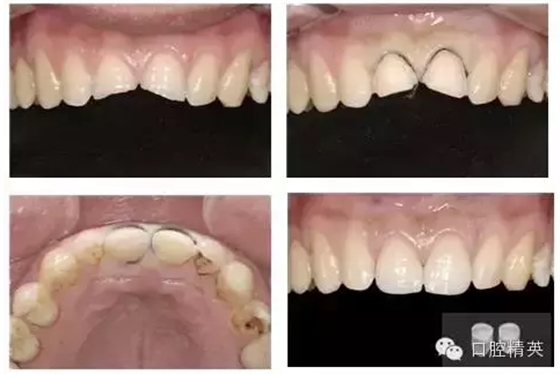

這是一個牙體缺損的患者,是一個高中生,即將升入大學,就是他最后高考完了以后,就是他來修復的,當時他一看到這個左上一是勁崩切咬缺損,右上一是差不多冠二分之一折斷,但是這個患者的牙髓是活的,就是說他的牙髓是有活力的,并沒有露出來。所以我們就,當時我們就考慮是采用什么樣性的修復方式?是做冠,那么我們就失活吧,因為你這樣牙體預備以后沒有足夠的規(guī)律。但是從患者年齡來講,還是盡量保持牙髓的活力,所以我們就設(shè)計一個貼面的修復,左上我們采用的是開窗式的全瓷貼面,右側(cè)我們就采用一個比較結(jié)實的,這是牙體預備以后的情況,這是我們修復完成以后的情況。就是從修復完成以后,從這個形態(tài)、顏色、功能,患者都覺得比較滿意。所以就是說,對這個病人的處理我們多了一種治療的思路,就是說在年輕紅牙牙體缺損以后,我們第一個要盡量的保存活力,第二個我們就采用一些粘貼修復的方法,也能達到患者一個滿意修復效果。